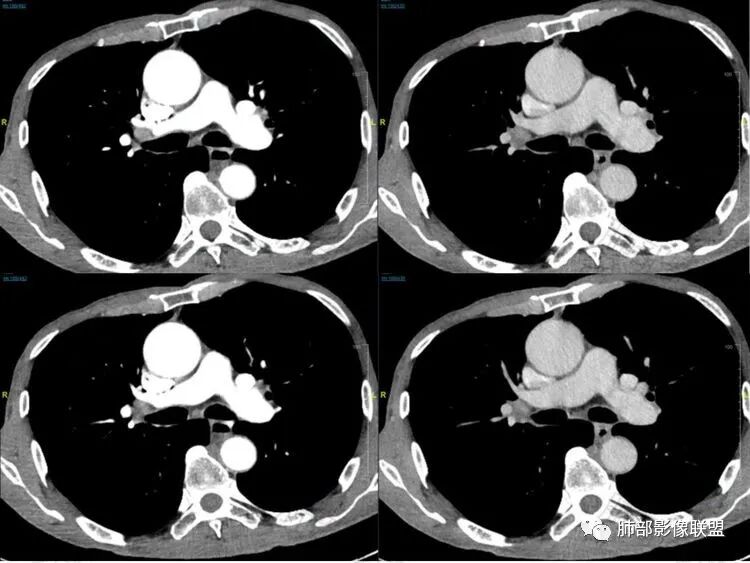

2娘小崽大、淋巴及血行转移早、冰冻纵隔及肺门、血管脂肪间隙消失

因为病灶侵袭力强,病灶易沿淋巴道、间质及心血管间隙等结构侵犯并密切挤压上述结构,常常能够观察到脂肪间隙消失。易于出现冰冻纵隔。原发灶与肺门转移灶可形成哑铃状外观,甚至转移灶体积大于周围原发灶,有人称之为“娘小崽大”。早期病灶有时很小甚或隐匿,仅能看到转移灶,或转移淋巴结与原发灶融合分界不清。病变向肺门延续的串珠样淋巴结转移也是SCLC的典型特点。

血管包埋征

病灶侵袭力强大,早期沿粘膜下疏松结缔组织及血管旁间隙扩散,包绕血管,血管会受压变形,因为小细胞癌破坏力弱,血管没有被破坏,所以仅仅表现为包埋浸润,但血流面光滑。

乏血供,沼泽样坏死

、罕见空洞

病灶肿瘤密集而供血血管相对不多,密度较均匀,轻度强化,呈乏血供,有时候可以坏死,坏死不彻底,坏死区分散而较小,呈沼泽样坏死,很难造成引流支气管的破坏,所以空洞罕见。

6边缘圆钝、光整,未见毛刺

神经内分泌肿瘤边缘通常圆钝,而且SCLC或周围没有任何促纤维结缔组织反应,质地软,所以边缘圆钝、没有毛刺。